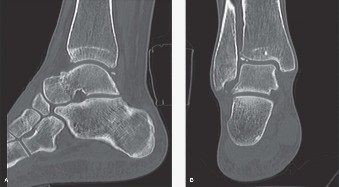

Figure 5–60 A, B: Sagittal and coronal CT scan images of ankle showing anterior tibial and talar osteophyte formation and multiple loose bodies.